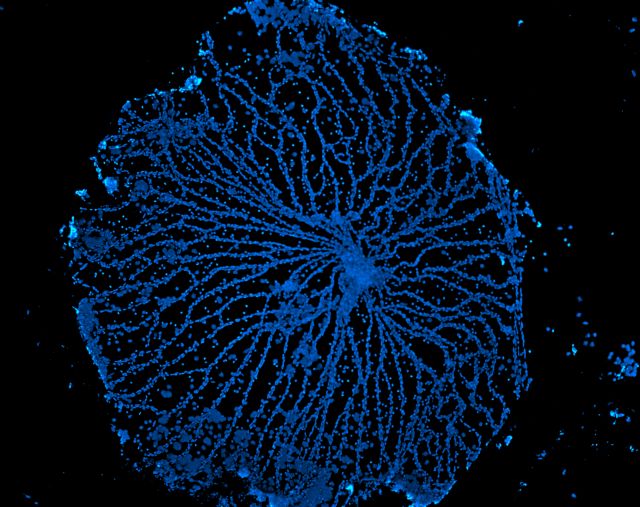

Κατά τη διάρκεια του σχηματισμού των οφθαλμών το έμβρυο αναπτύσσει αρχικά ένα δίκτυο αιμοφόρων αγγείων, τη λεγόμενη αγγείωση του υαλώδους, η οποία συμβάλλει στην τροφοδότηση του αμφιβληστροειδούς χιτώνα κατά την ανάπτυξή του. Καθώς όμως η αγγείωση του αμφιβληστροειδούς σχηματίζεται και ολοκληρώνεται, η αγγείωση του υαλώδους υποχωρεί ώστε να μην εμποδίζει την όραση.

Προς μεγάλη έκπληξη των ερευνητών κάτι τέτοιο δεν συνέβη στα έμβρυα των ποντικών που αναπτύσσονταν στο σκοτάδι, οδηγώντας σε βλάβες στον αμφιβληστροειδή και προβλήματα όρασης. «Εδώ δεν έχουμε κάτι ανεπαίσθητο, πρόκειται για μια μεγάλη επίδραση στον τρόπο με τον οποίο αναπτύσσεται ο αμφιβληστροειδής, ο οποίος φαίνεται ότι απαιτεί να περάσει φως μέσα στο σώμα» ανέφερε ο καθηγητής Ρίτσαρντ Λανγκ του Νοσοκομείου Παίδων του Σινσινάτι, εκ των επικεφαλής της μελέτης.